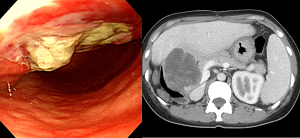

[Duodenal invasion of embryonal cell carcinoma of liver]